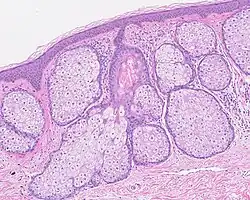

Multiples glandes sébacées volumineuses réalisant une hyperplasie sébacée.

- L'hyperplasie sébacée (voir Sebaceous hyperplasia (en)) est une prolifération excessive des cellules dans les glandes, visible macroscopiquement sous forme de petites papules sur la peau, particulièrement sur le front, le nez et les joues[28].